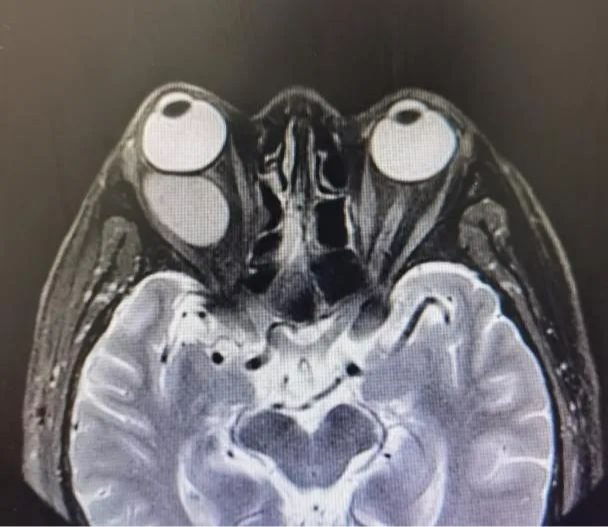

实力附院 | 高难度“拆弹”!附院眼科成功摘除眼眶巨大血管瘤

眼眶内的血管瘤就像一枚潜伏着随时会夺走人视力的“定时炸弹”,而眼科医生就像“拆弹专家”,需要承担极大的风险在复杂的神经血管中小心谨慎地将“炸弹”移除。